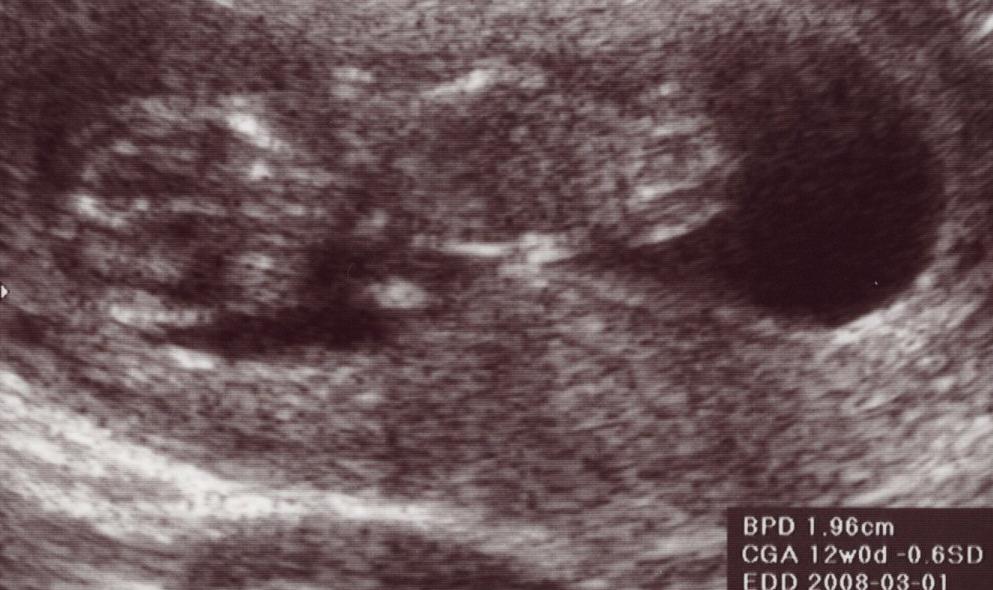

仕事の都合で9w0dには行けず、今日になってしまった。

今、大体3ヶ月半目。

妊娠初期に行う色んな検査を受けた。